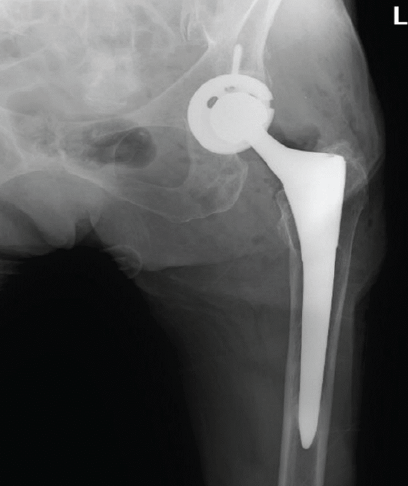

Irreducible Periprosthetic Hip Dislocation Due to Muscular Entrapment with Concomitant Sciatic Nerve Involvement

Zachary Fuller , Tuckerman Jones , Jeremiah Thomas , Mathew Weintraub , Jared Preston , Anand Patel

………………………………p.143-146